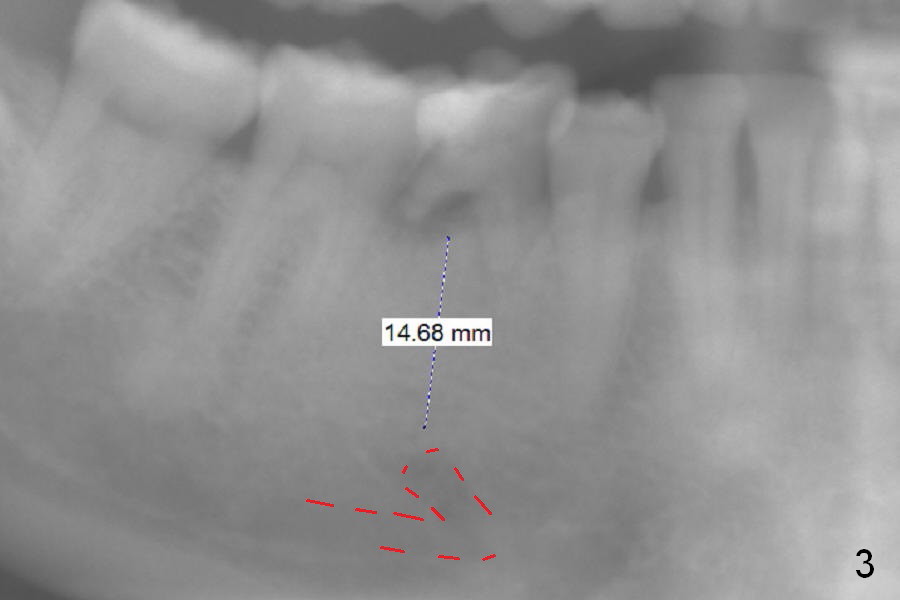

A 39-year-old woman has periodic mobility and pain of the lower right 2nd primary molar. It appears that the mesiodistal width of the tooth has decreased in the last 7 years (Fig.1,2). After extraction and Clindamycin/10 drops of 1:1000 Epinephrine gauze for 3 times, use LR plastic quadrant tray and PVS to take impression of the socket for education purpose. Try using Magic Expanders, but Magic Drills will be most likely used to finalize the osteotomy, since the bone density does not seem to be low. The initial depth will be 11 mm for IBS implant (Fig.3).